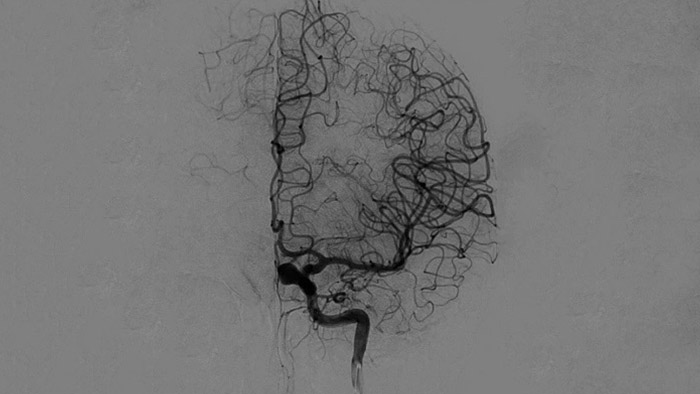

ClarityIQテクノロジーを使用した2D DSA

ClarityIQは、DSA撮影中の自動体動補正機能や、リアルタイム画像最適化処理により鮮明な画像を医師します。これにより、脳卒中治療において信頼性の高い画像での意思決定行うことができます。

高品質のDSA画像により、血栓が完全に回収されたかどうか、血栓の断片が脳内で遠位に分散しているかどうかを評価できます。また、ペナンブラへの血流の回復を確認し、治療前後の血流のチェックをすることができます。